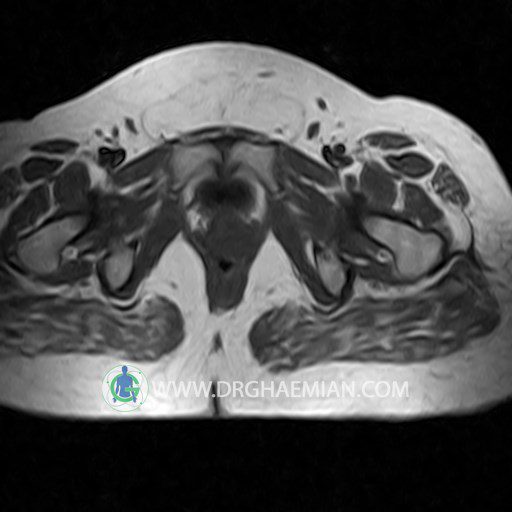

پزشکان اغلب از تصویربرداری ام آر آی برای تشخیص و درمان عارضه های پزشکی که فقط با استفاده از اشعه ایکس یا میدان مغناطیسی و امواج رادیویی قابل مشاهده است، استفاده می کنند. دستگاه ام آر آی تصاویر دقیق از ساختار های داخلی بدن ایجاد می کند. در این کیس کیست بارتولین لگن و تجمع دورمقعدی و کیست ساده ایی در تخمک چپی دیده می شود.

Technique : coronal STIR , coronal T2 , Axial T1 , axial T2 .

The femoral heads and acetabula are normal shape , signal intensity and the femoral heads are well covered by the acetabular margins .

The joint spaces are of normal width without fluid collection .

the articuler surfaces are smooth and congruent and show normal cortical thickness .

there are no marginal osteophytes or subchondral signal changes .

The bone marrow shows normal signal intensity , especially in the femoral head and neck .

Each femoral shaft has normal margins and contains a normal bone marrow signal .